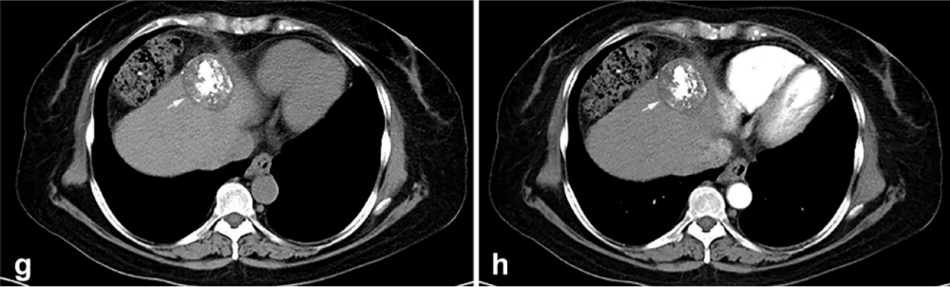

背景:由于一些原因,位于膈肌附近的腫瘤的熱消融在技術上具有挑戰性。首先,術中計算機掃描和超聲檢查無法清晰顯示射頻消融/微波消融切緣。第二,消融過程中不利的針分布和過熱可能導致肝包膜破裂,并對膈、肺和心臟造成嚴重損傷。第三,即使使用人工腹水,仍有9~22%的患者因肝周粘連或腫瘤位置靠近肝表面而導致膈肌熱損傷。冷凍消融可能是毗鄰膈肌的HCC的一種有前途的治療方法,因為在消融過程中使用CT和US可以很好地顯示腫瘤邊緣。盡管一些研究評估了在高危區域使用冷凍消融治療HCC,但很少有研究針對膈肌臨近區域。

① 術后 1 月腫瘤治療反應:冷凍消融術后一個月腫瘤疾病控制率達95.9%。